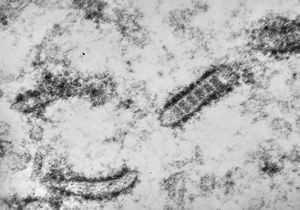

M,21y. | annulate lamellae - intracranial germinoma